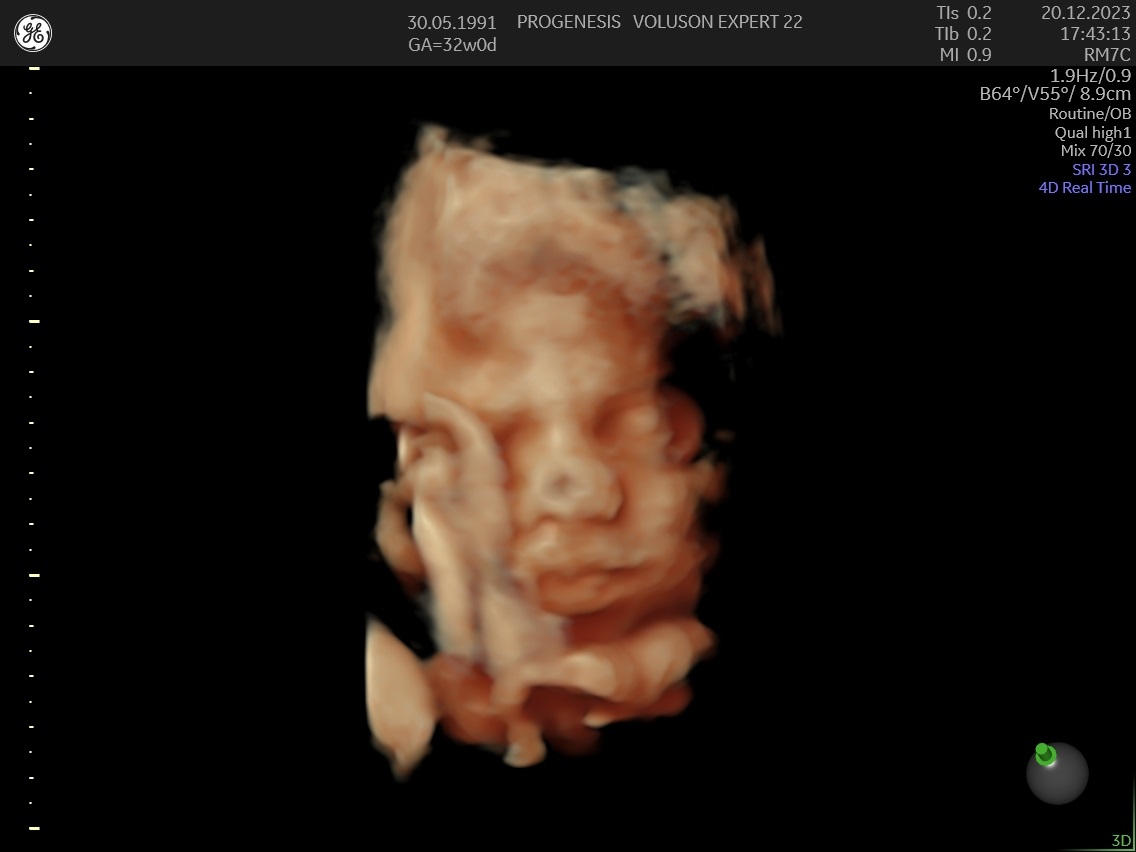

3D/4D LIVE Υπερηχογράφημα

Το 3D/4D LIVE είναι μια νέα τεχνολογία υπερήχων που δημιουργεί εικόνες του εμβρύου σε τρισδιάστατο ή τετραδιάστατο χώρο. Οι εικόνες αυτές είναι πιο ρεαλιστικές από τις παραδοσιακές εικόνες υπερήχων και δίνουν στους γονείς μια πιο ολοκληρωμένη εικόνα του μωρού τους.

Σε πιθανά ανατομικά προβλήματα του εμβρύου μπορούν να βοηθήσουν στην κατανόησή τους από τους γονείς.

Ωστόσο, οι εικόνες 3D/4D LIVE δεν μπορούν να αντικαταστήσουν τις παραδοσιακές εξετάσεις υπερήχων.